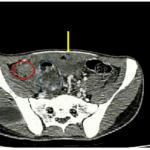

Case lâm sàng: Điều trị miễn dịch kết hợp thuốc kháng tăng sinh mạch cho bệnh nhân ung thư biểu mô tế bào gan tại trung tâm y học hạt nhân và ung bướu – BV Bạch Mai

Case lâm sàng: Điều trị miễn dịch kết hợp thuốc kháng tăng sinh mạch cho bệnh nhân ung thư biểu...